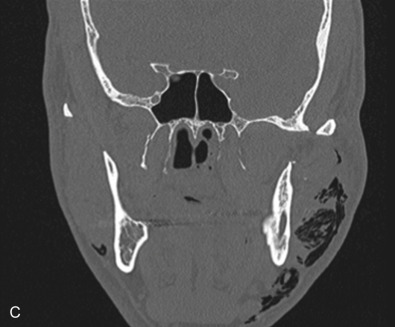

The gold standard for radiographic evaluation is thin-slice helical computed tomography (CT). Midface fractures are confirmed by axial, coronal, and sagittal views. The degree of comminution, bone loss, and detailed images of the fracture patterns can be assessed and juxtaposed to surrounding soft tissue structures. 3D reconstruction, when utilized, can aid in visualizing the complex 3D anatomical orientation of fracture fragments that occur in Le Fort injuries and facilitate reconstructive planning.

Le Fort III fractures generally consist of a combination of fractures that involve the palatine bones, the maxilla, the pterygoid plates, the nasal bones, lacrimal bone, and zygomas; they essentially separate the face along the base of the skull. The fracture pattern extends through the nasofrontal suture along the medial wall of the orbit, through the inferior orbital fissure and the lateral orbital wall to the zygomaticofrontal suture. In addition, the zygomaticotemporal suture is separated. The fracture extends across the sphenoid bone resulting in dysjunction at the pterygoid plates ( Figs. 1.13.16 and 1.13.17 ). The septum is separated from the cribriform plate of the ethmoid. Pure Le Fort III fractures are rare, and in actuality, most are ZMC fractures in conjunction with Le Fort I and II fractures lending the appearance of a comminuted “Le Fort III.” The force is delivered from the orbital level, resulting in craniofacial dysjunction. The fracture is generally more comminuted and more extensive on the side of force application.